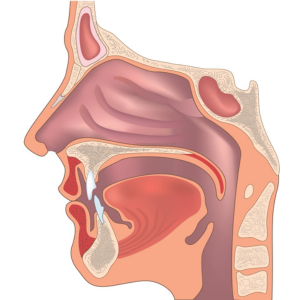

É comum relato de pressão na região do nariz, um pouco de sensibilidade nos dentes de ancoragem (apoio do aparelho), ou mesmo pressão no palato.